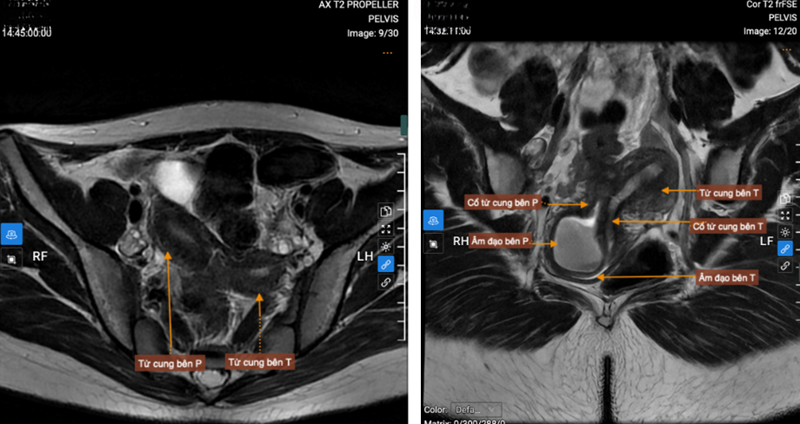

Trên MRI cho thấy 2 sừng tử cung, 2 cổ tử cung riêng biệt, vách ngăn âm đạo

Âm đạo bên phải ứ dịch (kích thước 75x40mm), âm đạo bên trái xẹp, theo dõi có lỗ thông nhỏ, vị trí tắc cách tiền đình âm đạo 9mm

Kết quả siêu âm ổ bụng và MRI tiểu khung ghi nhận: hình ảnh tử cung đôi hoàn toàn; vách ngăn âm đạo kèm ứ đọng dịch máu trong nửa phải âm đạo; thận phải loạn sản đa nang, lạc chỗ.